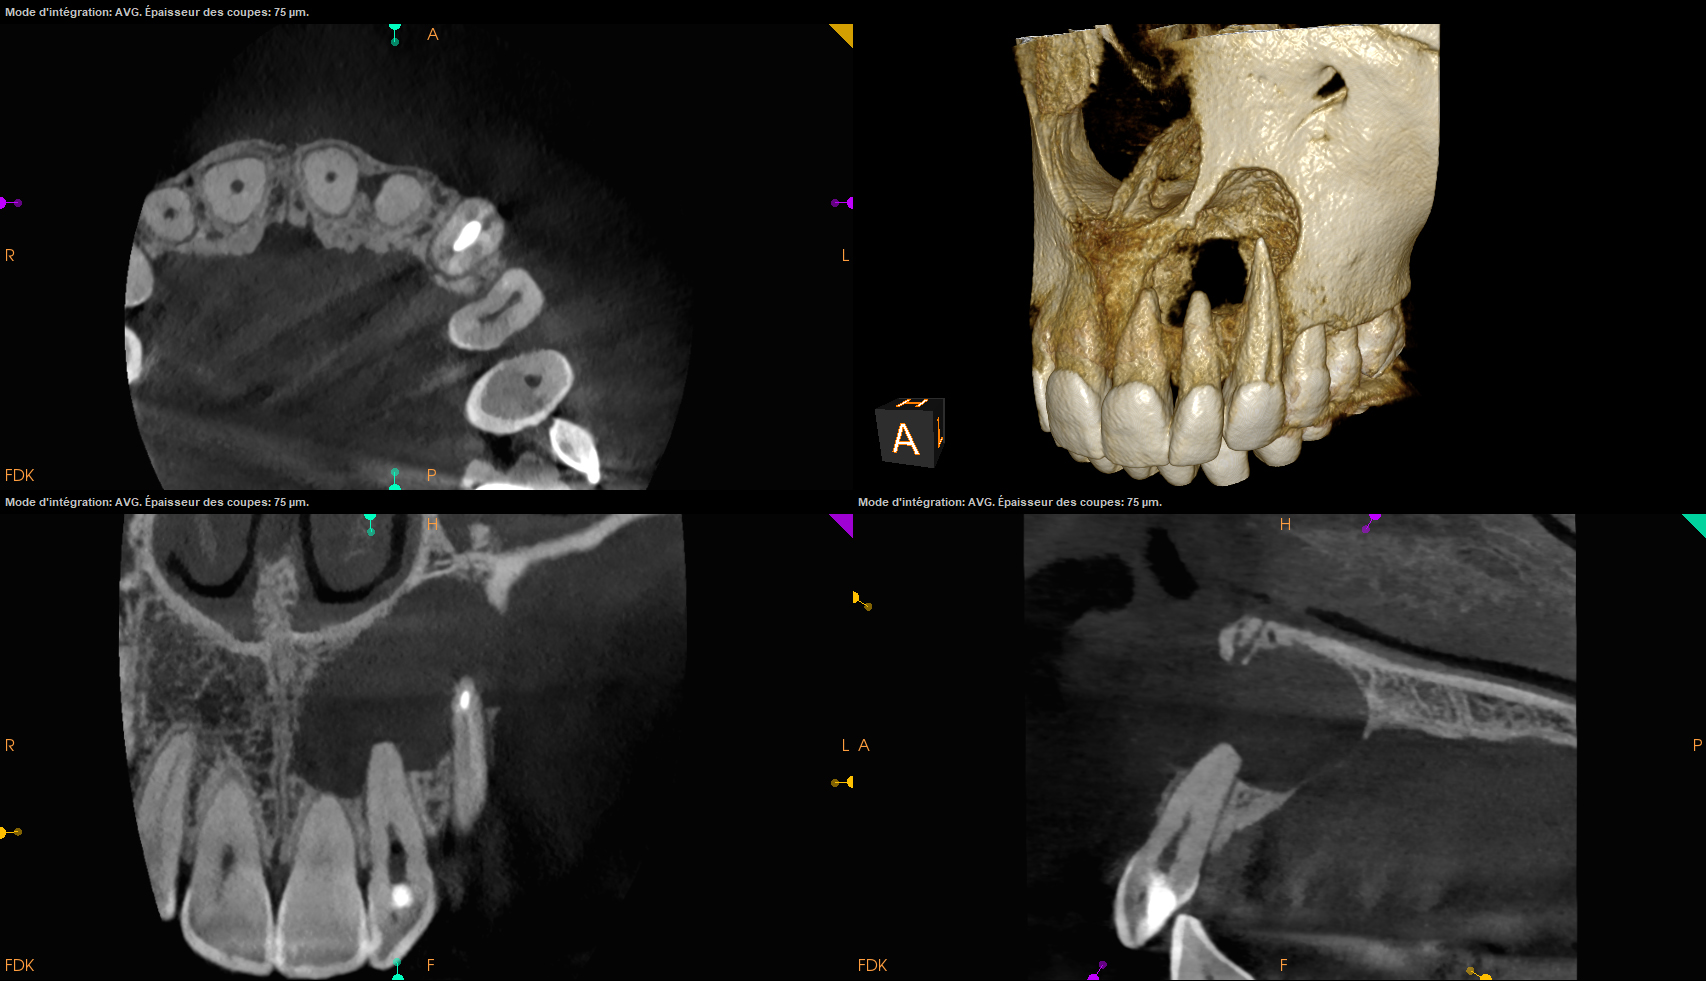

Las impresiones digitales han revolucionado el proceso de creación de prótesis dentales, ofreciendo una precisión y eficiencia sin precedentes. Gracias a esta avanzada tecnología, podemos capturar cada detalle de la anatomía dental de nuestros pacientes, lo que se traduce en una adaptación perfecta de las prótesis.

Las impresiones digitales eliminan la necesidad de moldes tradicionales, lo que no solo mejora la comodidad del paciente, sino que también acelera el proceso de fabricación. Con un escaneo digital de alta definición, conseguimos imágenes detalladas que permiten a nuestros técnicos de laboratorio diseñar prótesis personalizadas que se ajustan perfectamente.

- Escaneo Intraoral Preciso: Utilizamos escáneres intraorales de alta resolución para obtener una representación digital exacta de la dentadura del paciente.

- Digitalización y Diseño: Las impresiones se digitalizan y se transforman en modelos 3D para un diseño protésico preciso.